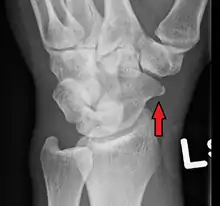

A subtle scaphoid fracture

A more obvious scaphoid fracture on a scaphoid view X ray